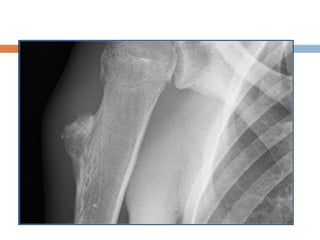

Osteochondroma

 Common

 Development malformations rather than true

neoplasms

 Originate within the periosteum as small

cartilaginous nodules

 Produced by progressive endochondral

ossification of a growing cartilaginous cap

 Growth of lesion parallels that of the patient and

stops once skeletal maturity is reached

 Most lesions found during the period of rapid

skeletal growth.

 Single lesion—90%

 Site– may involve any bone formed in cartilage

usually found on metaphysis of long bone

near the physis (distal femur, proximal tibia,

proximal humerus)

Diagnosis

 X-ray

 Eccentric bony outgrowth from metaphyseal

region of long bone composed of cortical and

medullary portions which are continuous with

the cortex and medulla of the underlying bone

 Cap not visible

 Usually sufficient